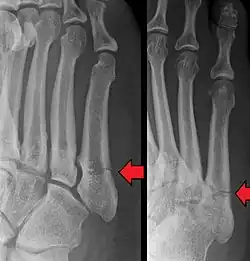

1896 and 1902 – Jones fracture and published radiograph

On 7 February 1896, Welsh orthopaedic surgeon Robert Jones (and Oliver Lodge) took a radiograph of the wrist of a 12-year-old boy to locate a bullet that could not be found by probing. The X-ray required a 2-hour exposure, but successfully demonstrated the bullet lodged in the third carpometacarpal joint. This case was published in The Lancet in February 1896,[30] the first published clinical radiograph.[31]

Robert Jones described the fracture of the fifth metatarsal which bears his name in the Annals of Surgery in 1902. In his paper, Jones described the fracture in a series of six patients, the first of which was himself.[32]